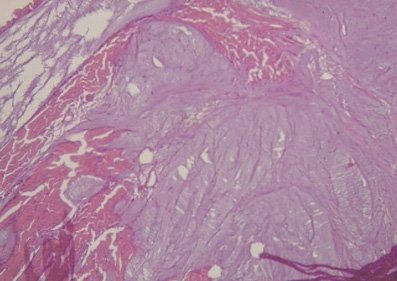

Análisis anatómico e histologíco del miocardio. En la secuencia del análisis histológico del miocardio desplegado (figura 27) se demuestra la orientación longitudinal, de acuerdo con la continuidad de los segmentos que tiene su conformación espacial, tanto en la cara interna como en la externa en cada uno de ellos. Las fibras tienen direcciones paralelas en ambas superficies (interna y externa) de cada uno de los segmentos. La superposición de los segmentos que implica la conformación helicoidal resulta indispensable para lograr la torsión miocárdica, acción fundamental de la mecánica cardíaca que no sería posible con la estructura de malla (entrecruzamiento de fibras miocárdicas). En esta estructura helicoidal se produce un rozamiento en sus superficies de contacto, lo que implica que presenten un sistema lubricante que facilita la movilidad autónoma de ellos con menor gasto de energía, tema que se analizará en esta Proposición.

Ningún segmento de la histología secuencial en la continuidad longitudinal del miocardio en nuestras investigaciones presentó una disposición en malla. En la cara externa de la parte distal del segmento descendente, al girar a nivel del ápex y transformarse en ascendente, los miocardiocitos generan en los cortes planimétricos una arquitectura disímil a la cara interna en su orientación, único sitio donde sucede esta situación. Esta disposición se halla dada en el ápex, en donde el trayecto en espiral de las fibras miocárdicas que se desplazan desde la periferia hacia el centro determinan un cambio brusco de la dirección, ya que las fibras subepicárdicas se vuelven subendocárdicas (figura 27), superpuestas como las tejas en un techo, que es lo que evidencia la imagen comentada. Esta configuración es lógica para la demostración de la disposición helicoidal pues sucede en el sitio donde el miocardio transforma en forma brusca su dirección de descendente en ascendente. En el resto la disposición es siempre paralela. El miocardio continuo se asemeja a la cinta de Moebius dado el cambio progresivo de la angulación en las fibras transformándose de epicárdicas en endocárdicas (164).

Esta investigación evidencia que el miocardio no se estructura como una malla sino en forma de músculo continuo en espiral (figura 28) (217). El concepto que se ha esgrimido de malla fue elaborado a partir de la superposición de segmentos a través del plegamiento de la hélice miocárdica. Si se desenrolla el miocardio con la técnica de disección apropiada se obtiene un grosor similar en toda la extensión del músculo, evidenciando que su continuidad es real. Plegado, se encuentra que el grosor del ventrículo derecho es la mitad que la del ventrículo izquierdo, ya que el primero se halla compuesto por solo un segmento del músculo, mientras que el segundo presenta adosamiento de dos segmentos. Su disección, por los planos de clivaje comentados, siempre finaliza en la misma estructura de desplegamiento. La pregunta es la siguiente: ¿cómo es posible repetir disecciones obteniendo siempre el mismo resultado y no concluir en la existencia de una continuidad de las fibras miocárdicas?